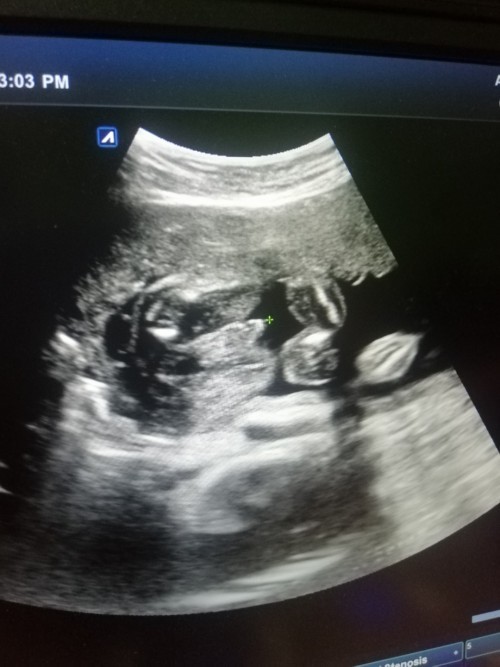

ผช.ครับ

ชายค่ะ

ผช.ค่ะ